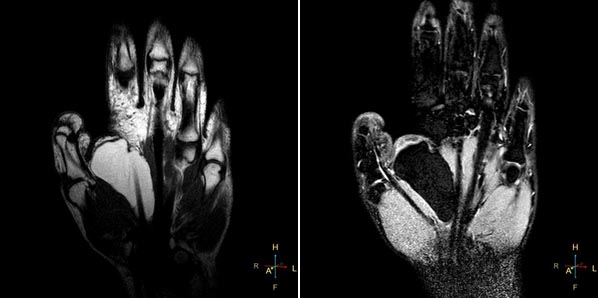

МРТ кисти руки назначают для диагностики различных заболеваний и травм, таких как тендинит, артрит, опухоли или повреждения мягких тканей. Врачи отмечают, что этот метод исследования позволяет получить детализированные изображения, что значительно повышает точность диагностики. Процедура проводится безболезненно и не требует специальной подготовки. Пациенту необходимо лечь на стол аппарата, который затем перемещается в магнитное поле. Важно, чтобы во время сканирования пациент оставался неподвижным, чтобы избежать размытия изображений. Врачи подчеркивают, что МРТ является безопасным методом, не использующим ионизирующее излучение, что делает его особенно ценным для диагностики у детей и беременных женщин.

Магнитно-резонансная томография (МРТ) позволяет точно диагностировать заболевания, травмы и другие факторы, вызывающие боль и нарушения в функционировании кистей рук. На снимках видны проблемы с кровообращением и воспалительные процессы. Даже незначительные повреждения, такие как растяжения и разрывы сухожилий и связок, становятся видимыми благодаря этой методике.

Магнитно-резонансная томография (МРТ) кисти руки – это высокоинформативный метод диагностики, который позволяет врачам получить детальные изображения мягких тканей, суставов и костей. Люди отмечают, что МРТ помогает выявить различные патологии, такие как травмы, воспаления, опухоли и дегенеративные изменения. Процедура проводится безболезненно и обычно занимает от 15 до 30 минут. Пациенты лежат на специальном столе, который задвигается в магнитный туннель. Важно, чтобы во время исследования сохранялась неподвижность, чтобы изображения были четкими. Многие отмечают, что процесс не вызывает дискомфорта, хотя некоторые могут испытывать легкое беспокойство из-за замкнутого пространства. Результаты МРТ помогают врачам назначить правильное лечение и следить за динамикой заболевания.

Врачи могут создавать трехмерные модели поврежденных костей и суставов кисти, что особенно важно, когда проблемная зона находится в труднодоступном месте. Это касается, в первую очередь, заболеваний лучезапястного сустава, так как запястье состоит из восьми костей, расположенных друг над другом.